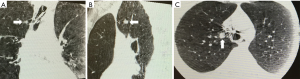

The miniaturization of the radial probe has allowed for imaging of peripheral lesions beyond the segmental airways. In this capacity, the ultrasound probe, albeit typically without a balloon, can be placed through the working channel of the bronchoscope and extended into the periphery to identify intrapulmonary nodules (6). Utilization of this technique has evolved in several ways. The radial probe can be extended through the bronchoscope to identify the lesion, leaving the bronchoscope in the appropriate subsegment and replacing the probe with biopsy tools. The addition of a guide sheath may improve diagnostic yield (7). The radial probe can be directed to the nodule via a sheath catheter and after the probe has been removed biopsy of the nodule can be done with or without fluoroscopy through the catheter that has been directed to the nodule. Using the latter technique, diagnostic yield for peripheral pulmonary nodules 2–3 cm can be as high as 72%, at single centers versus yields as low as 20% for bronchoscopy alone (7,8). If a concentric view is obtained, where the nodule encircles the probe, the diagnostic yield improves to 84% and has similar, if not improved yield, compared to computed tomography (CT) guided biopsy, with fewer complications (Figure 1) (7,9). When RP-EBUS has been combined with electromagnetic navigational bronchoscopy (ENB) the diagnostic yield for peripheral nodules is increased versus either technique alone (10,11). TBNA of the peripheral pulmonary nodule can also improve diagnostic yield by nearly 10% versus brush biopsy or forceps biopsy (12).